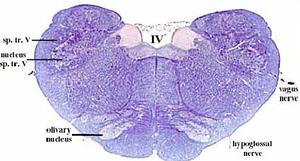

secciones transversales a diferentes niveles del tronco del encéfalo mostrando la localización de los núcleos neuronales aferentes de los nervios craneales

AFERENTES:

Somatoaferentes:

generales (GSA): boca y cara

-especiales (SSA): sentido de la visión y oído

Visceroaferentes:

- generales (GVA): recogen sensación de faringe y laringe

-especiales (SVA): sentido del gusto y del olfato

correspondencias entre la localización de los núcleos neuronales en diferentes cortes.